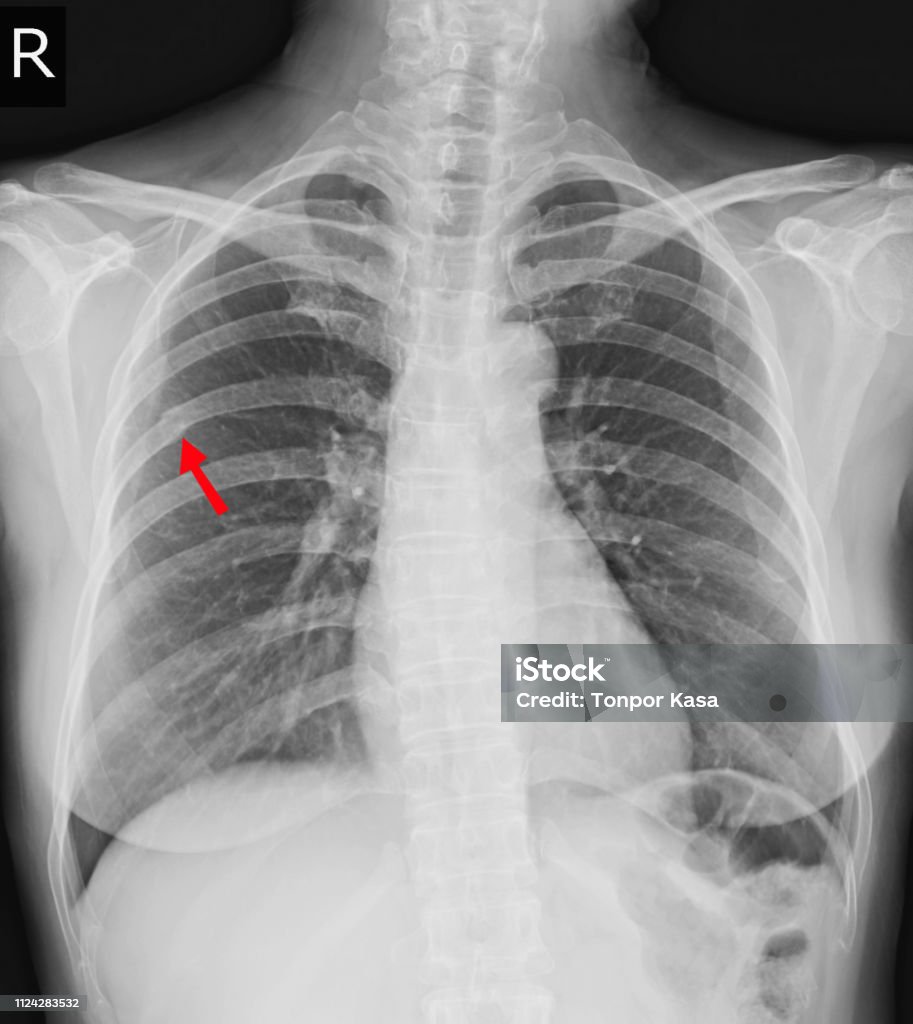

Foto de Peito Raiox Da Fratura Bem 6ª Costela E Face Lateral De Possível Fratura Da Costela

Fratura de costela na radiografia de tórax... YouTube

Raio x fraturas deixadas clavícula, costela anterior 2, costela posterior 4,5 aspecto lateral da